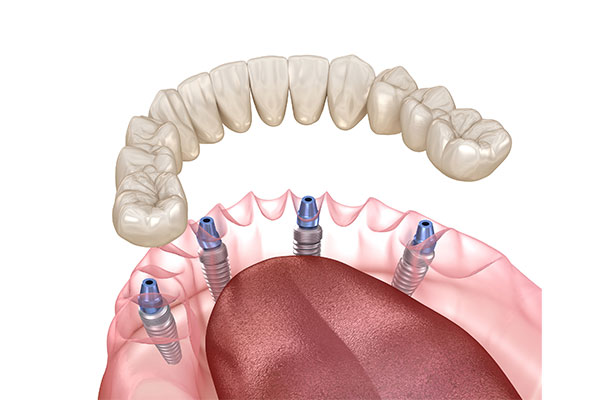

オールオン4

オールオン4は、片顎に4本のインプラントを埋め込み、その上に固定式の人工歯を取り付ける治療法です。

骨が少ない方でも対応できることが多く、治療期間が短く、手術当日に仮歯が入れられるため、治療中でも見た目や食事のストレスが少ないのが特徴です。